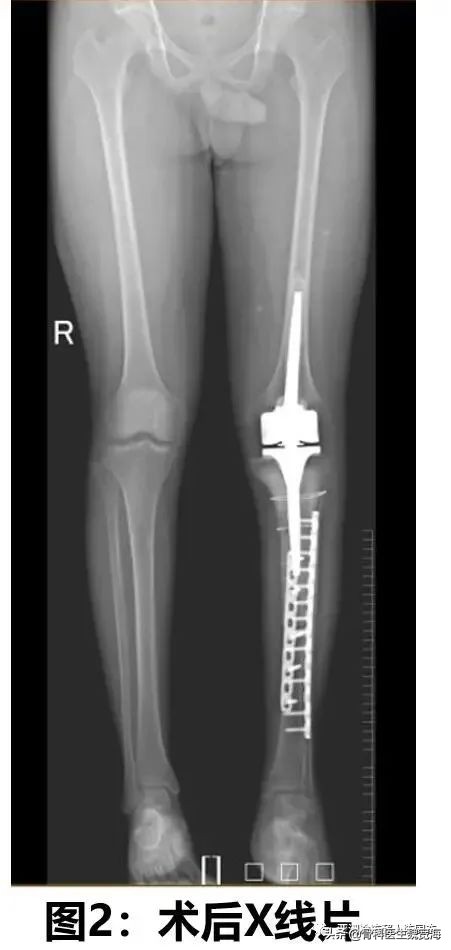

患者是一名19岁的大男孩。左腿痛到南方医院骨科看病时,X光显示肿瘤已经累及了左侧胫骨超过一半的长度。尤其特别困难的是,胫骨的关节面也受累了,这在骨肉瘤中是不多见的。这种情况下,截肢是一种常规的选择。但是患者本人和妈妈都希望尽全力不截肢。经过和家属的充分沟通,医生制定了新辅助化疗+手术+术后化疗的标准治疗方案。 术前两周期新辅助化疗后,经过一周的精心准备,在南方医院创伤骨科余斌主任的亲自指导下,骨肿瘤亚专业组按计划实施了“左胫骨骨肉瘤瘤段切除+液氮冷冻灭活+瘤段回植+肿瘤型膝关节假体置换+胫骨内外侧双钢板内固定术”。手术经历了八个小时的连续奋战,顺利完成。术后20天,患者顺利出院。将进入下一步的综合治疗。